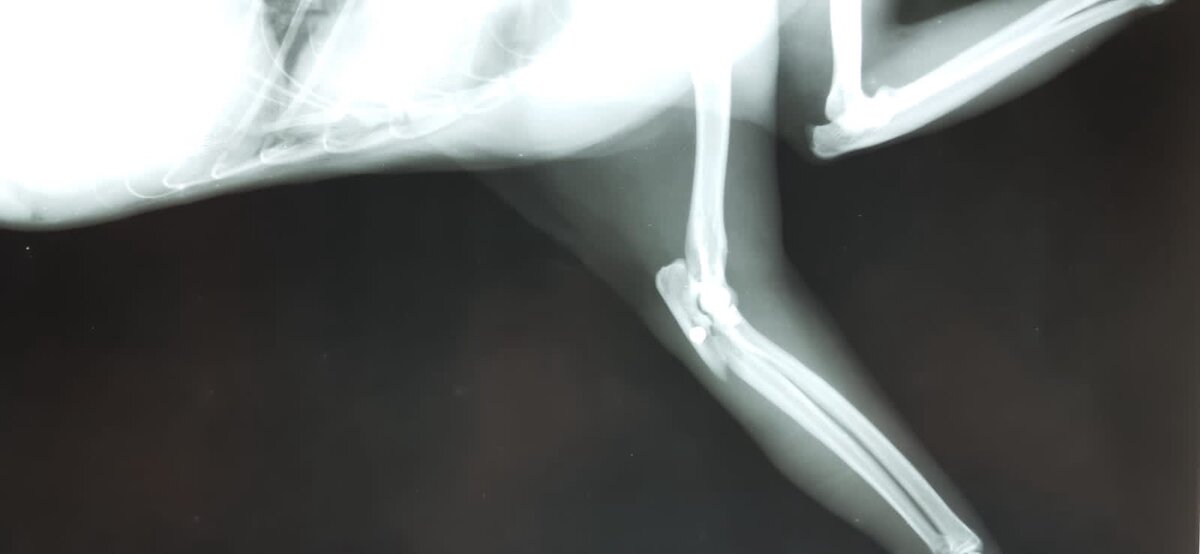

пуля в локтевом суставе